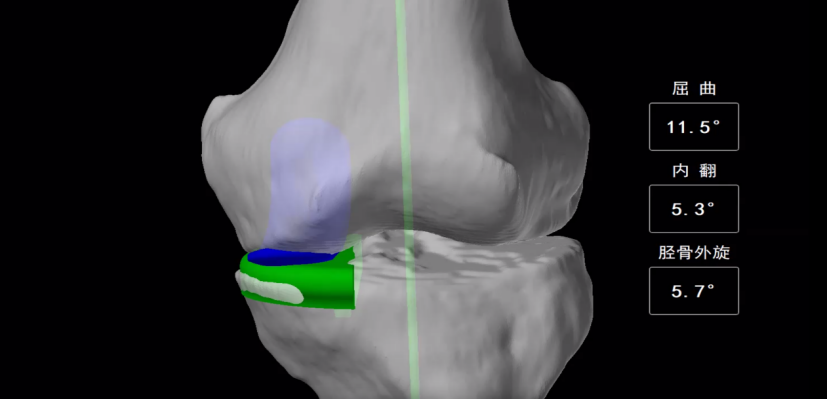

△机器人辅助下膝关节单髁置换术(UKA)治疗

手术通过完成CT数据扫描生成3D骨骼模型。手术中,许长鹏副主任医师团队利用AI智能机器人进行辅助操作,精准安放假体,平衡关节和合适张力。术后第一天,龙奶奶便能下地行走。

在机器人辅助下,医生能将高难度的手术做到十分精细。在手术开始的时候,机器人需要通过探针寻找标记点,反复地校准直到所有点位通过并显示绿色。多个维度上的校准使得手术十分精准。